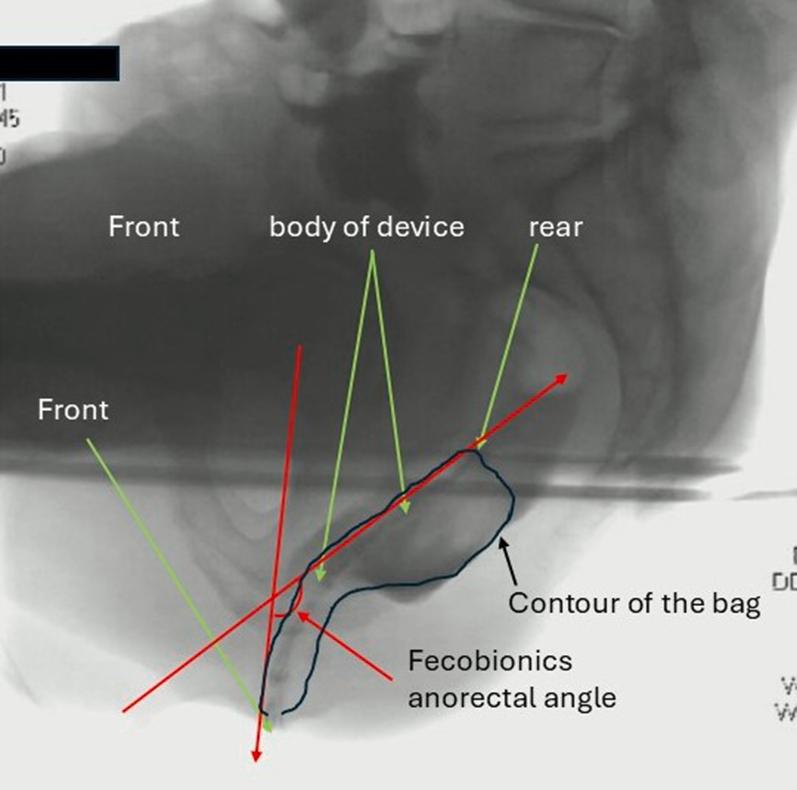

Electronic Measurement of the Anorectal Angle Versus Radiographic Assessment.

Gastro Hep Adv. 2025 Jun 10;4(9):100718. doi: 10.1016/j.gastha.2025.100718. eCollection 2025.